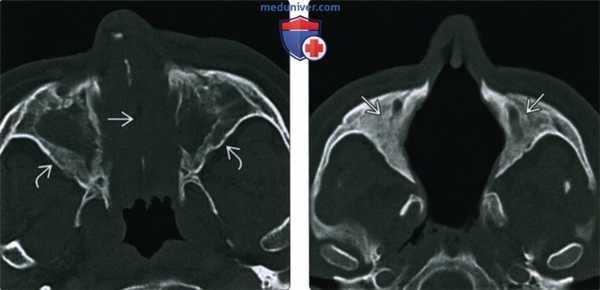

(Слева) При аксиальной «костной» КТ определяется узловой мягкотканный компонент, заполняющий полость носа; снижена пневматизация верхнечелюстных пазух. Носовая перегородка перфорирована, стенки пазух утолщены и склерозированы, что типично для ГПА.

(Справа) При аксиальной «костной» КТ в случае далеко зашедшего ГПА определяется тотальная центральная деструкция полостей носа, включая перегородку, раковины, наружные стенки. Верхнечелюстные пазухи блокированы утолщенной костью.

(Слева) На аксиальной КТ в костном окне полость носа полностью заполнена мягкими тканями, пневматизация обеих верхнечелюстных пазух тотально снижена. Определяется перфорация носовой перегородки утолщение и склероз стенок пазух - все изменения сопоставимы с ГПА.

(Справа) На аксиальной КТ в костном окне у пациента с поздней аадией ГПА определяется деструкция костных структур полости носа, в т.ч. носовой перегородки. Верхнечелюстные пазухи облитерированы вследствие утолщения костной ткани.